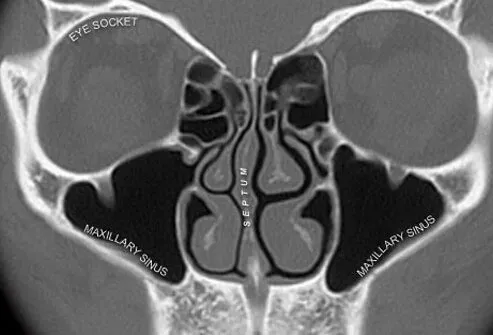

Vos sinus sont des espaces d'air dans votre crâne et vos os du visage qui composent la partie supérieure de vos voies respiratoires de votre nez dans votre gorge. Les sinus sont dans votre front (sinus frontaux) à l'intérieur de vos pommettes (sinus maxillaires) et derrière le nez (sinus ethmoïdes et sphénoïdes).

Qu'est-ce que la sinusite?

L'inflammation des tissus qui remonte les sinus est appelée sinusite. Les infections avec des virus ou des bactéries ou des allergies provoquent la plupart des cas de sinusite.